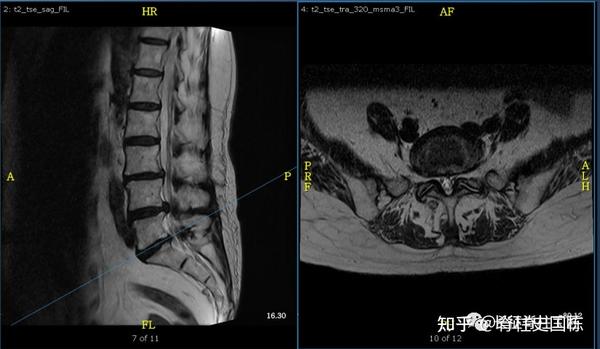

脊柱管狭窄症 Mri

脊柱管狭窄症 Mri : 断面の脊柱管腔は純粋に客観的な評価となり,クモ膜 下腔の狭小化と術前の脊柱管狭窄症による症状の相関 表1 各椎間・撮影方法での脊柱管前後径比 l1/2椎間 l2/3椎間 l3/4椎間 腰椎mri 0.8660.830.679